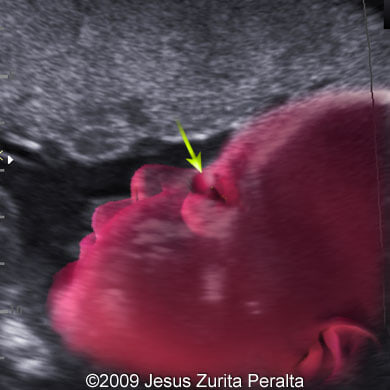

The following images show a case of the dacryocystocele diagnosed at 30 weeks of a pregnancy.

Images 3, 4: 30 weeks; the image 3 demonstrates a parasagittal scan of the fetal face running through the left canthus with the cystic structure representing the dacryocystocele (arrow). The image 4 demonstrates a fusion of the image 3 and a drawing explaining the position of the fetal head and location of the dacryocystocele (arrow).